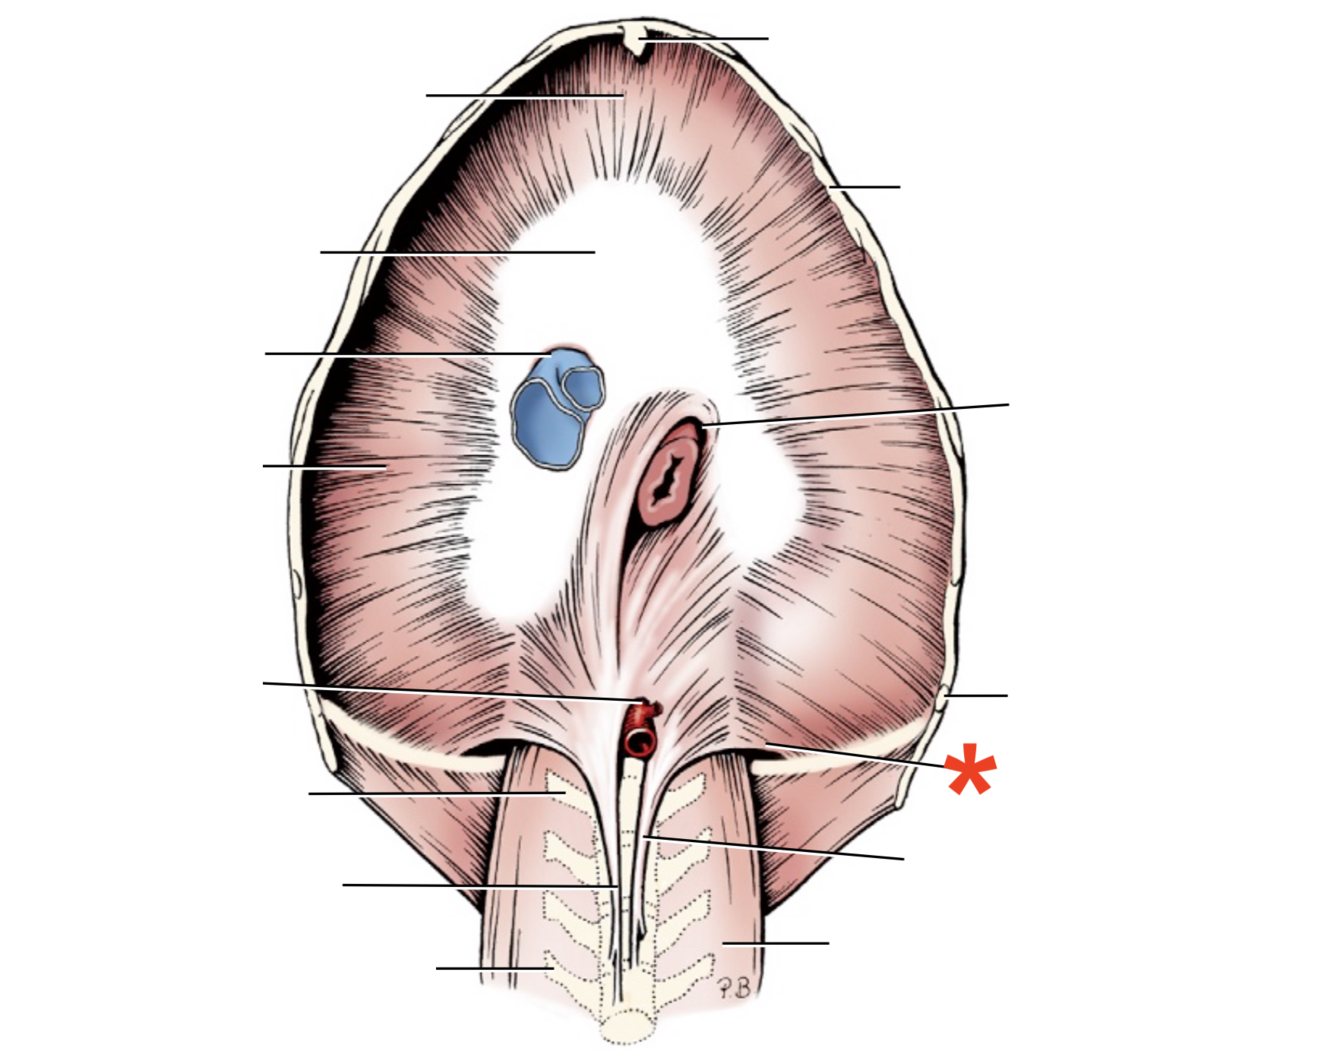

Name given to the most cranial part of the diaphragm.

Cupula Diaphragmatis

Q

Pars sternalis

Q

Foramen vena cavae

Q

Pars costalis

Q

Hiatus aorticus

Q

Arcus lumbocostalis

Q

Hiatus oesophagus

Q

Crus sinistrum

Q

Crus dextrum

Q

Centrum tendineum

Q

Corona muscularis